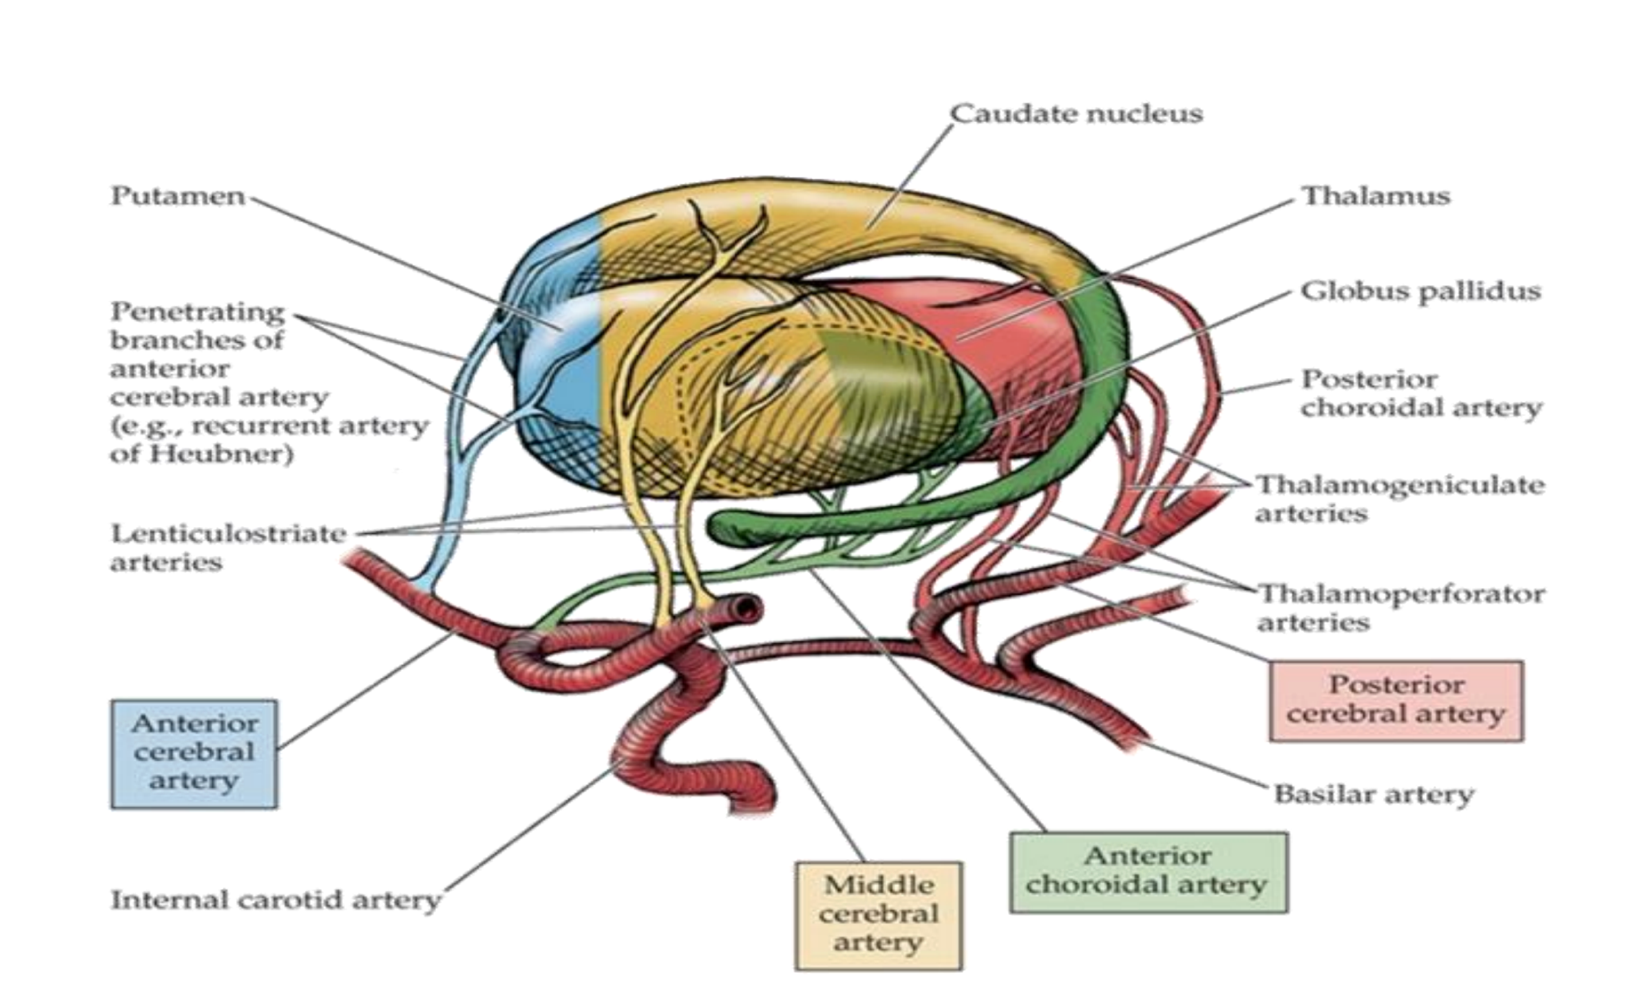

What supplies blood to the caudate nucleus?

Branches from anterior cerebral artery (anterior part)

Boddy of the middle cerebral artery

Tail of the anterior choroidal artery.

What supplies blood to the putamen?

Middle cerebral artery

Branches from anterior cerebral artery (anterior part)

What supplies blood to the globus pallidus?

Lenticular striate arteries

Anterior choroidal of internal carotid & internal capsule

What supplies blood to the thalamus?

Lenticulostriate arteries from the middle cerebral artery